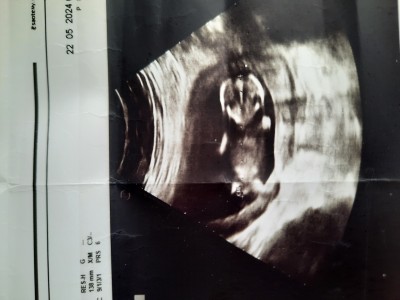

Doktor erken diye tahmin yapmadı ama fotoğraf verdi cinsiyeti nedir sizce?

Erkek.